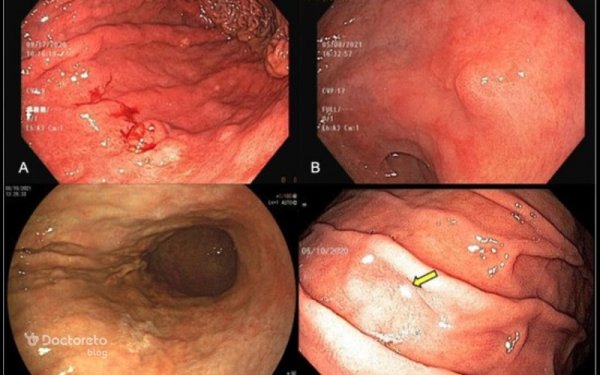

تودهها و ضایعات پیشرفته

در مراحل پیشرفته، تصاویر اندوسکوپی وضوح بیشتری دارند و پزشک میتواند تودههای بزرگتر یا زخمهای عمیق را مشاهده کند:

-

تودههای برجسته و نامنظم که به مخاط اطراف چسبیدهاند

زخمهای وسیع با لبههای غیرهمگن و خونریزی سطحی

مناطق فرورفته یا گود افتاده که به دلیل از بین رفتن بافت ایجاد شدهاند

تغییرات رنگ شدید، از صورتی روشن تا قهوهای یا خاکستری

این تصاویر به پزشک کمک میکنند تا محل دقیق نمونهبرداری برای بیوپسی مشخص شود.

استفاده از تکنولوژی پیشرفته در تصویربرداری

امروزه اندوسکوپهای مدرن مجهز به فناوریهایی مانند نبیلایزیشن، فلورسنت و اندوسکوپی با بزرگنمایی بالا هستند که جزئیات بافتی مخاط را بهتر نشان میدهند. این فناوریها باعث میشوند تغییرات کوچکتر و ضایعات پیشسرطانی سریعتر شناسایی شوند.